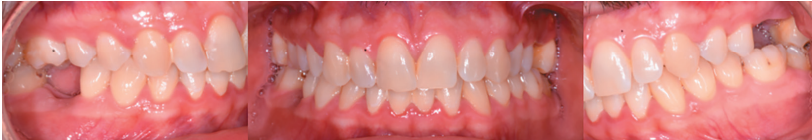

There were no medical-surgical antecedents of interest in his medical history, without known drug allergies or unhealthy habits. No relevant data was found on the extra oral examination. In the intraoral examination, non-restorable teeth were seen in the 2.6 and 4.6 position and the presence of retained lower third molars. (Figures 1 and 2).

The extraction of 4.6 and 2.6 and the curettage of the apical processes were planned, and the autotransplant of the left upper third molar (2.8) to sustain the 2.6 (Figure 5) was suggested to the patient.